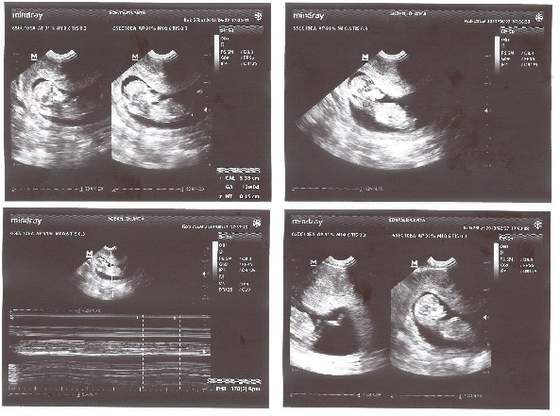

nasza dzidzia 5.38 cm szczęściazdrowiutkie zwiercone maleństwo - na ostatnim zdjęciu noga w całej okazałości

same pochwały od Pana gin.

jestem spokojna i mega szczęśliwa